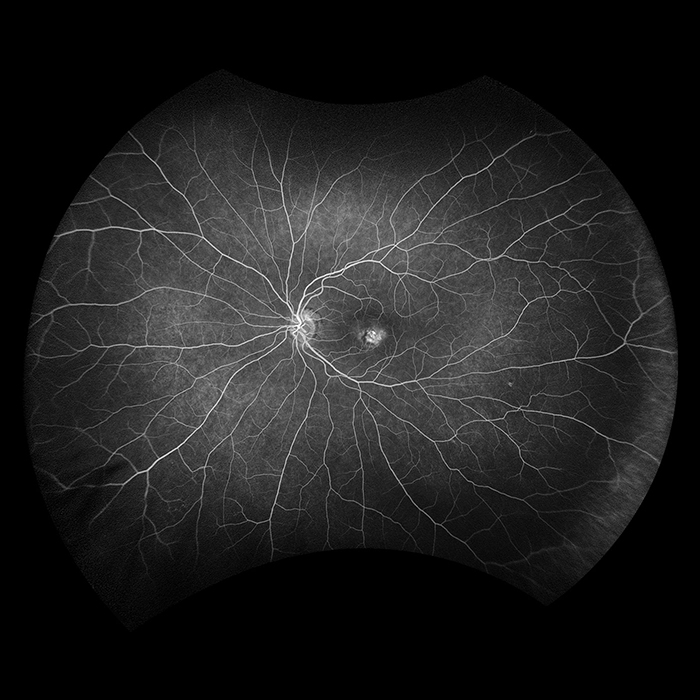

Optos führte die UWF™ (Ultra-Weitwinkel Bildgebungstechnologie) ein mit der Augenärzte Augenpathologien entdecken, diagnostizieren, dokumentieren und behandeln können, die sich zuerst in der Peripherie zeigen und mit konventionellen Untersuchungsmethoden und Geräten zunächst unentdeckt bleiben können. Jedes unserer Geräte für hochauflösende Ultra-Weitwinkel-Bildgebung erfasst mittels Laser Scanning Technologie in einer einzigen Aufnahme mehr als 80 % bzw. 200° der Netzhaut. Eine vollständige Liste unserer Geräte mit Ultra-Weitwinkel Bildgebungstechnologie finden Sie unten.

Silverstone ist das derzeit leistungsfähigste Gerät zur Untersuchung der Netzhaut. Als einziges Ultra-Weitwinkel-Bildgebungsgerät mit integriertem, geführtem Swept-Source-OCT liefert Ihnen Silverstone mit einer einzigen Aufnahme und in weniger als ½ Sekunde ein 200° optomap Bild der Netzhaut und ermöglicht zudem geführte OCT-Aufnahmen bis in die Peripherie der Netzhaut.

optomap kann die Erkennung von Pathologien sowie das Krankheitsmanagement nachweislich verbessern und für effizientere klinische Abläufe sorgen. Mit dem integrierten Swept-Source-OCT ermöglicht Silverstone nun die Untersuchung der Netzhaut vom Glaskörper bis hin zur choroidal-skleralen Grenzfläche.

Unser beliebtestes Produkt, California, wurde für die medizinische Bildgebung entwickelt und ist ein Standard für Netzhautscreening-Programme. California ist in verschiedenen Bildgebungsmodalitäten erhältlich. California erzeugt in weniger als ½ Sekunde ein 200°-Bild der Netzhaut mit nur einer einzigen Aufnahme von unübertroffener Klarheit und beeinflusst das Management von Krankheiten wie DR, AMD, Geografische Atrophie, und Uveitis